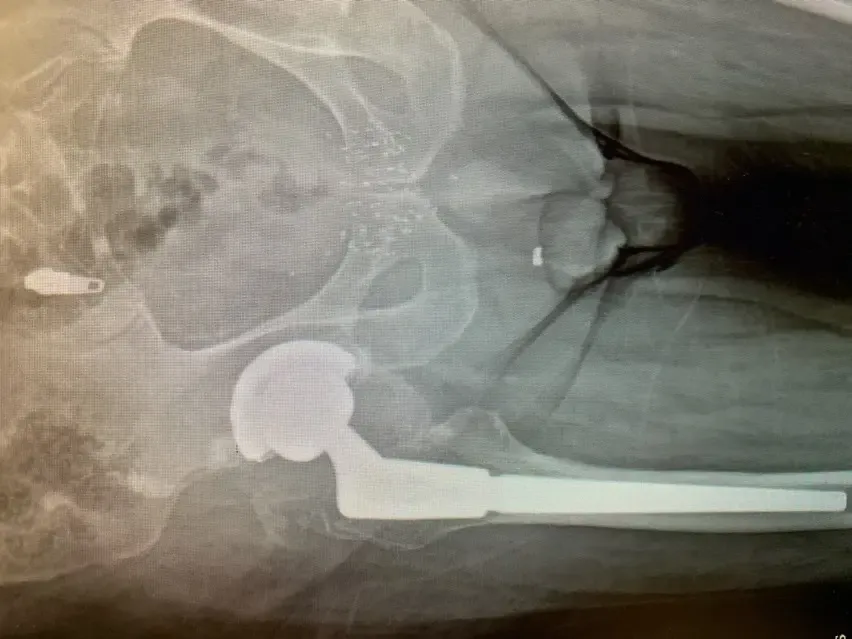

Retiramos cuidadosamente el componente femoral y el revestimiento plástico del componente acetabular; las pruebas de la carcasa metálica revelaron que era estable, por lo que se decidió que esta parte del procedimiento original permanecería intacta.

Preparamos e insertamos el componente femoral de revisión sin ningún evento y probamos componentes femorales de la cabeza con componentes de revestimiento acetabular para asegurar que la cadera permaneciera estable. Una vez satisfechos con el tamaño de los componentes, se colocaron los componentes definitivos y se completó el procedimiento.